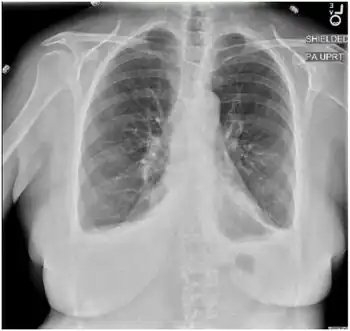

In a prior case of Bornholm disease the laboratory results showed the white blood cell count, hemoglobin, hematocrit, creatinine, liver function test (LFT), troponin, and creatine kinase (CK) were all within normal limits. The chest x-ray showed bilateral pleural effusions which resolved after infection. The erythrocyte sedimentation rate (ESR) and C-reactive protein (CRP) levels were found to be elevated. The electrocardiogram (EKG) did not show any abnormalities related to ischemia.[10]